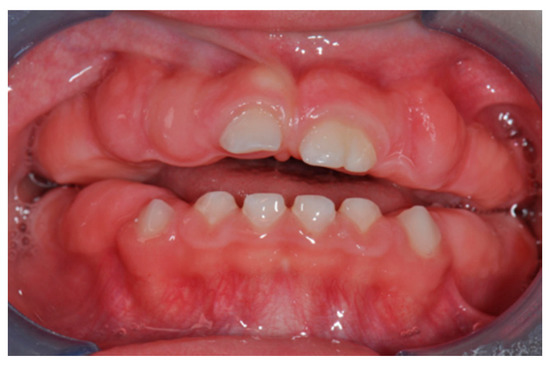

2.1. Patient Information

2.3. Therapeutic Intervention

3.1. Histological Characteristics